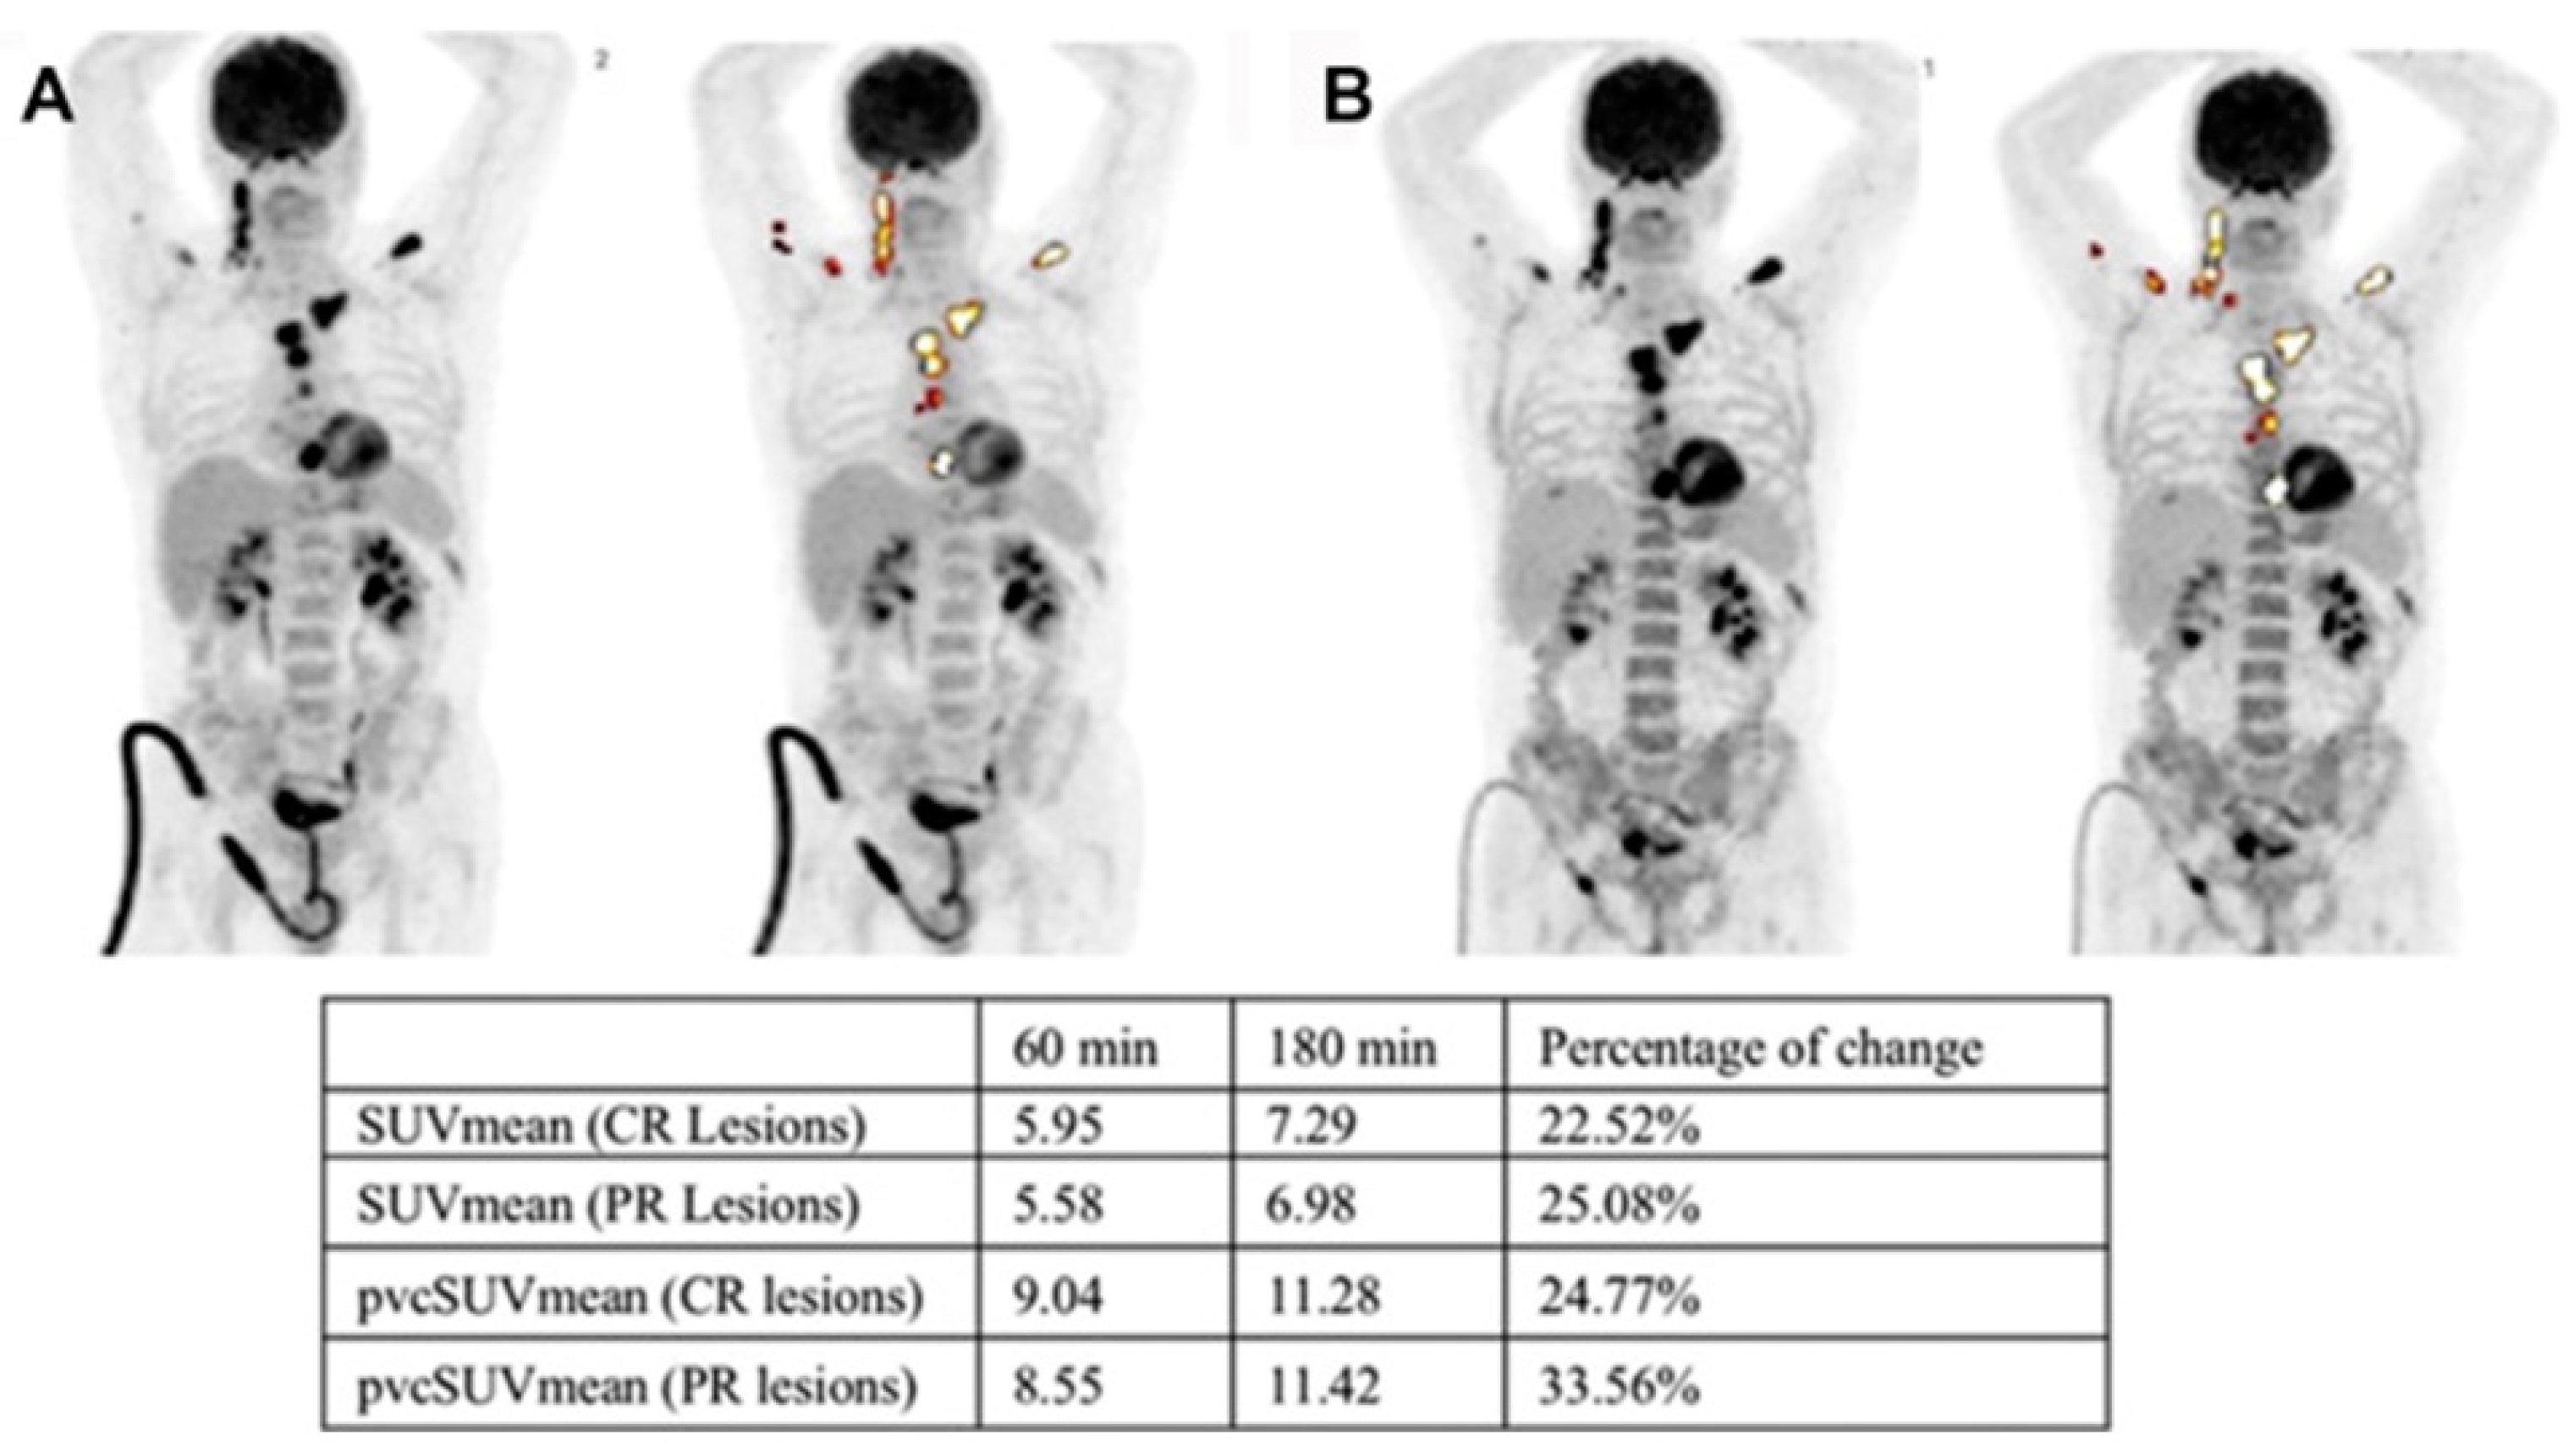

6. Dual-Time-Point Imaging (DTPI) in MM

- Zirakchian Zadeh, M.; Raynor, W.Y.; Østergaard, B.; Hess, S.; Yellanki, D.P.; Ayubcha, C.; Mehdizadeh Seraj, S.; Acosta-Montenegro, O.; Borja, A.J.; Gerke, O.; et al. Correlation of whole-bone marrow dual-time-point 18F-FDG, as measured by a CT-based method of PET/CT quantification, with response to treatment in newly diagnosed multiple myeloma patients. Am. J. Nucl. Med. Mol. Imaging 2020, 10, 257–264. [Google Scholar] [PubMed]

- Taghvaei, R.; Oestergaard, B.; Zadeh, M.Z.; Raynor, W.; Paydary, K.; Acosta-Montenegro, O.; Nielsen, A.; Werner, T.; Abildgaard, N.; Hoilund-Carlsen, P.F.; et al. Correlation of Dual Time Point FDG-PET with Response to Chemotherapy in Multiple Myeloma. J. Nucl. Med. 2017, 58 (Suppl. 1), 188. [Google Scholar]